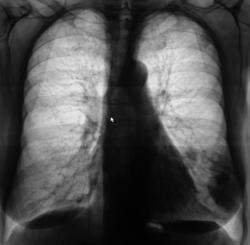

Пациентка направлена в рентгеновский кабинет врачом терапевтом для рентгенографии органов грудной полости. Пациентка предъявляет жалобы на наличие "сухого" кашля, субфебрильную температуру.

Произведена рентгенография в стандартных проекциях, томография в левой боковой проекции.

Похоже на метастазы.

Может я выдумываю, но не нравятся эти округлые тени, вероятно - метастазы.